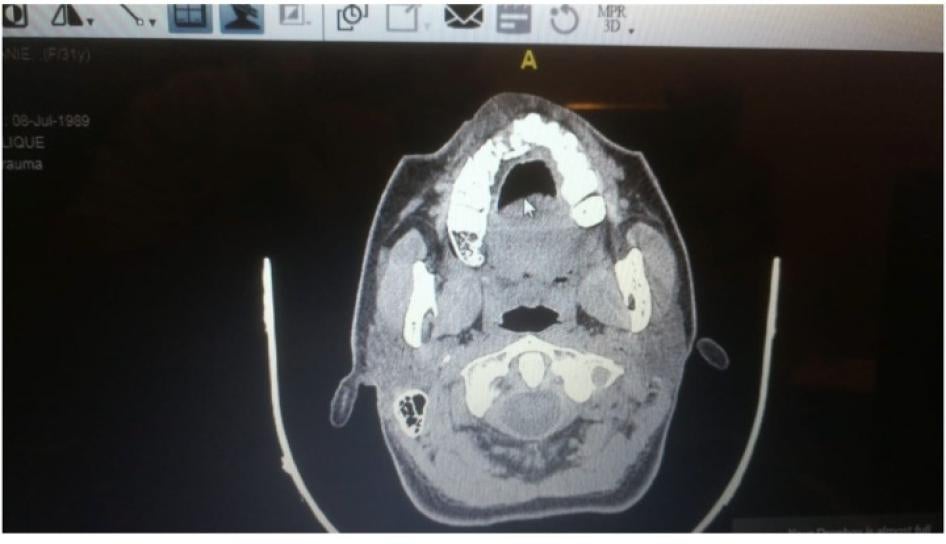

أطلقت قوات الأمن رصاصة مطاطية على صدر ربيع زينو وعلى وجهه من مسافة قريبة، ما تسبب في انغراس غلاف الرصاص وكرتها في خده. © 2020 ربيع زينو

قال ربيع زينو (26 عاما) إنه كان خلف مبنى فيرجن السابق المطل على موقف السيارات بين الساعة 5 و5:30 بعد الظهر، ورأى عناصر من الجيش، وحرس مجلس النواب، ومسلحين بلباس مدني يصوبون أسلحتهم باتجاهه وآخرين تجمعوا في نفس المكان. كان المتظاهرون يرمون الحجارة على الموقف ويتقدمون، في حين كانت القوى الأمنية تطلق الغاز المسيّل للدموع والرصاص المطاطي على المتظاهرين وفي اتجاههم.

قال ربيع إنه بينما كان ينحني ليلتقط حجرا، وجّه عنصر أمني يرتدي الزي العسكري الأخضر بندقيته على وجهه مباشرة وأطلق عليه الرصاص المطاطي من مسافة أقل من مترين. أدار ربيع وجهه بسرعة واستقرت الرصاصة المطاطية في خده. أطلقت القوى الأمنية الرصاص المطاطي على صدر ربيع أيضا ومؤخرته.

تظهر الأشعة السينية كسرا في عظم الفك العلوي لمتظاهرة بعد أن أصيبت برصاصة مطاطية. © 2020 خاص

في حادثة أخرى، أُطلقت رصاصة مطاطية من مكان انتشار القوى الأمنية بالقرب من كاتدرائية مار جاورجيوس وأصابت امرأة في وجهها. كانت واقفة في الساحة الملاصقة لجامع الأمين وأصيبت بينما كانت تدلي بمقابلة على قناة "الحرة". قال طبيب مطلع على حالتها إن الرصاصة المطاطية كسرت أسنانها وحنكها وخلعت عظم الفك العلوي، متسببة بضرر دائم في بنية العظم في وجهها. وأضاف إن الإصابة قد تسبب لها ألما دائما بسبب تمزق أعصاب أسنانها.